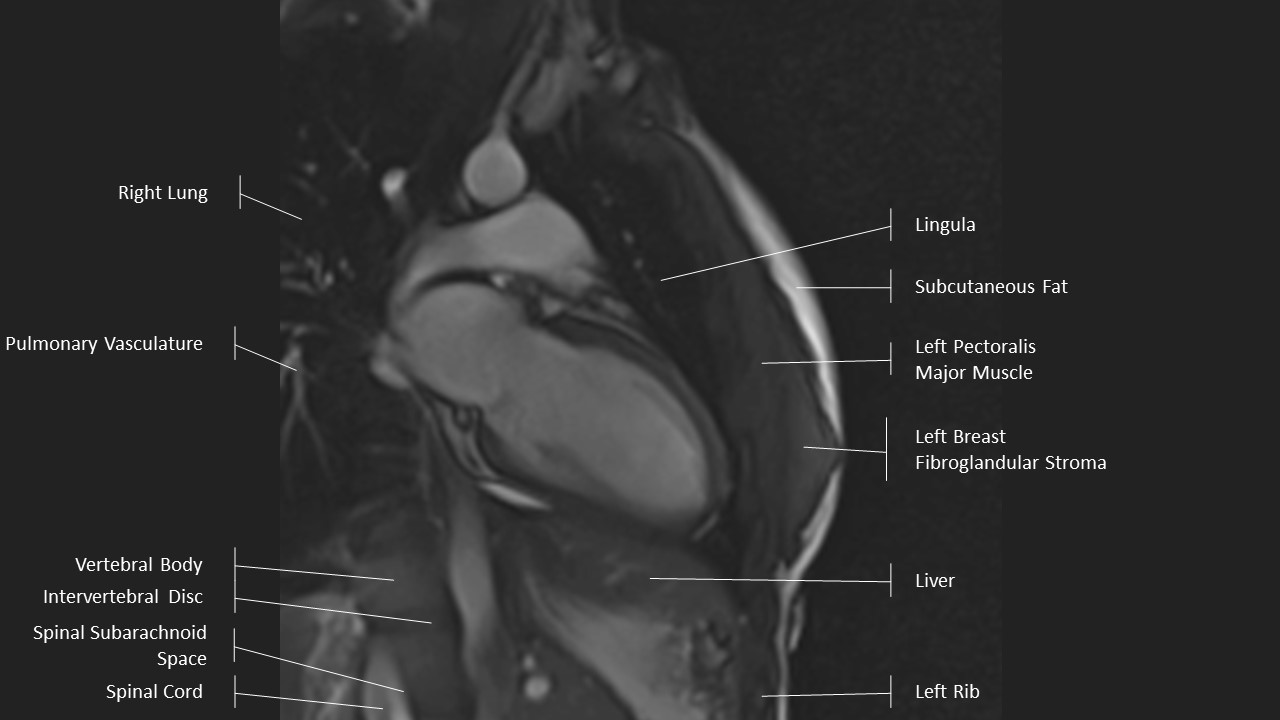

2 Chamber View